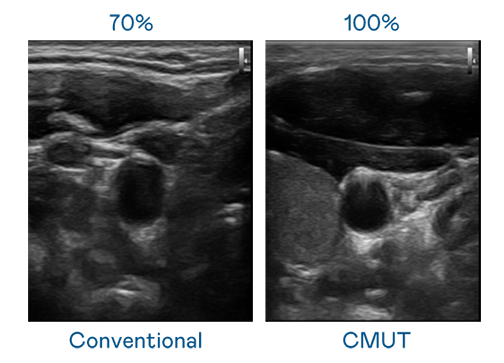

CMUT 技术是一种用电容式微机电元件来产生超音波讯号的技术。与传统 PZT 压电式技术相比,CMUT 频宽增加 30%,更宽频的超音波讯号让影像解析度大幅提升,是实现高影像品质医疗超音波扫描、促进精准医疗发展的关键技术。

超音波影像的解析度高低,首先取决于探头能发出的讯号频宽。尊龙时凯 CMUT 可提供高清晰的超音波讯号,提供高频宽、高灵敏度、影像纹理细节更高的超音波影像,协助医护人员缩短影像判读时间及利用精准的医疗影像进行诊断。